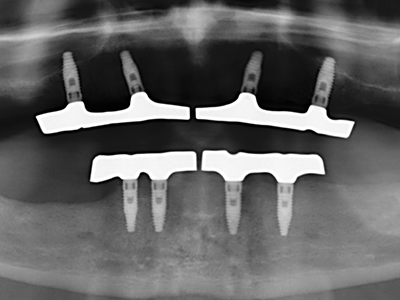

Indikation: Bone Splitting

Knochengewebe ist nicht nur rein mineralisch, sondern auch in wesentlichen Anteilen aus Kollagenfasern aufgebaut. Dies gewährleistet neben einer guten Druckfestigkeit eine gewisse Flexibilität, welche für die Durchführung von Augmentationen genutzt werden kann. Bei der klassischen Expansionsplastik im Sinne eines Bone Splittings wird der atrophierte Kieferkamm in seiner Längsachse gespalten und nach Erreichen einer ausreichenden Osteotomietiefe vorsichtig aufgedehnt (Abb. 13-16), idealerweise ohne den Kiefer wesentlich zu deperiostieren (Brugnami, Caiazzo et al. 2014, Stricker, Fleiner et al. 2014). Bewährt haben sich Schrauben- und Plattensysteme mit zunehmender Expansionsdistanz, um die beiden Knochenlamellen unterhalb der Bruchschwelle voneinander zu distanzieren. In der Regel werden Restknochenbreiten von mindestens 3-4 mm gefordert (Chiapasco, Zaniboni et al. 2006), um eine ausreichende Flexibilität und knöcherne Bedeckung der einzubringenden Implantate zu gewährleisten. Ggf. kann eine ein- oder beidseitige vertikale Entlastungsosteotomie die Flexibilität verbessern. Als Alternative zur klassischen Technik wurde eine Kombination mit weiteren augmentativen Techniken vor allem auf der bukkalen Seite beschrieben.

Mittels Piezosägen erfolgt die Anlage des Splittings besonders schonend und ohne wesentliche Dimensionsverluste, so dass sich keine signifikanten Unterschiede von Implantaten im gesplitteten Kiefer im Vergleich zum nicht defizitären Alveolarkamm gezeigt haben (Chiapasco, Zaniboni et al. 2006, Danza, Guidi et al. 2009). Gerade beim lokal begrenzten und tiefen Splitting ist jedoch stets auf eine ausreichende Wasserkühlung zu achten, um thermische Belastungen in den apikalen Osteotomiebereichen zu vermeiden.